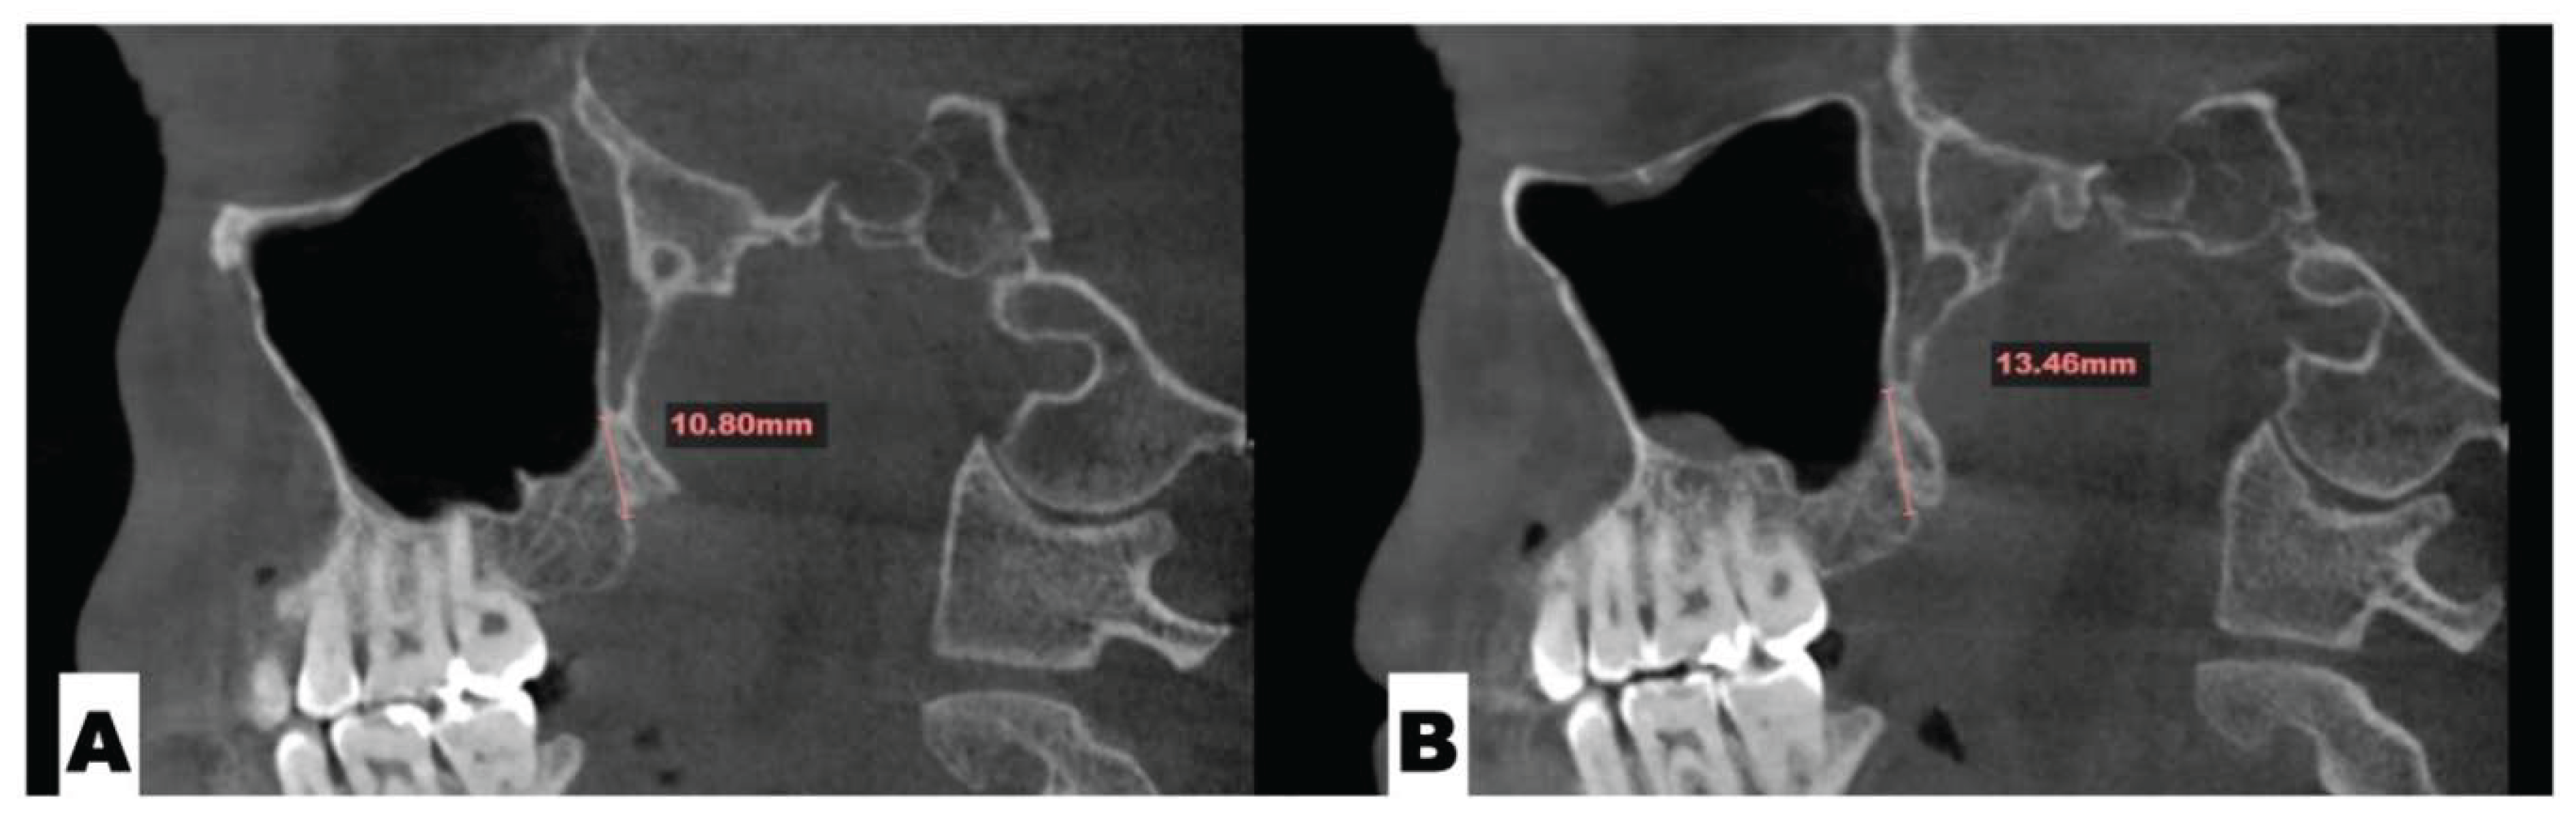

Background: While mini-screw-assisted rapid palatal expansion (MARPE) is effective for correcting maxillary transverse deficiency in adults, perimaxillary suture disarticulation—particularly at the pterygomaxillary junction—can be inconsistent. This study evaluates skeletal and dentoalveolar outcomes of a novel 3D-guided midpalatal piezocorticotomy-assisted MARPE protocol, focusing on expansion symmetry and pre-existing asymmetries. Methods: Three adult patients were retrospectively analyzed after treatment with 3D-guided midpalatal piezocorticotomy-assisted MARPE expansion and one with non-guided midpapalatal piezocorticotomy and MARPE expansion. Surgical guides were digitally designed using CBCT data to align with the nasal septum orientation in multiple planes. Perimaxillary suture disarticulation was measured pre- and post-expansion, and dentoalveolar changes were evaluated. Post-expansion asymmetries were addressed using directly printed aligners. Results: Complete midpalatal suture separation (mean 8.48 mm), involving both anterior and posterior nasal spine regions, was achieved in one patient. Bilateral pterygomaxillary disarticulation averaged 1.06–1.23 mm, resulting in forward–outward rotation of the nasomaxillary complex. Additional separation occurred at the frontonasal (2.03 mm) and vomeromaxillary (1–2 mm) sutures, with no significant changes in orbital or peri-orbital sutures. One patient presented with pre-existing dentoalveolar asymmetry, which intensified the perceived post-expansion imbalance but was successfully corrected with directly printed aligners. In the second case, 5.6 mm of suture separation resulted in a limited lateral nasal width increase (<1.5 mm), while maxillary base expansion exceeded 6 mm. A significant canine plane cant (1.2 mm) and divergent axial inclinations of the maxillary central incisors relative to the palatal plane were also observed. In the second case, a non-impactful palatal bone fracture with asymmetric displacement of the left palatine fragment was documented. After 16 months of aligner therapy, all cases exhibited favorable remodeling of the palatal structures, midpalatal suture, and alveolar processes, accompanied by improved dental alignment, occlusal plane symmetry, and mandibular dentoalveolar adaptation. The dento-alveolar expansion achieved in the third case over the course of 16 months of treatment was approximated at 4 mm. The fourth case showed consistent improvement with direct printed aligners after MARPE midpalatal diasrticulation of 11 mm after experiencing minor bone fracture. Conclusions: Human skulls exhibit considerable variability between the left and right sides, which can influence spatial balance. Pre-existing cranial asymmetries appear to be the primary contributors to asymmetry following MARPE treatment. Careful evaluation of dentoalveolar discrepancies and axial tooth inclinations is essential for preventing and managing potential asymmetric dental arch outcomes during the post-expansion phase. Although peri-maxillary bone fractures are relatively uncommon, their occurrence is influenced by multiple factors. Adjunctive techniques, such as 3D-guided midpalatal piezocorticotomy, show promise in significantly lowering the risk of intra-expansion peri-maxillary fractures.

| Suture nomenclature | Amount of disarticulation |

|---|---|

| Frontomaxillary | 2.5 mm |

| Pterygomaxillary | 1.06-1.23 mm |

| Frontonasal | 2.03 mm |